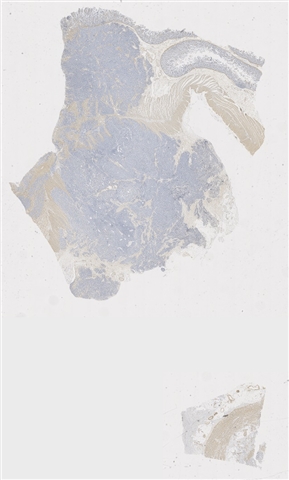

案例2 (6843)

患者详情: 因“反复便血一周“入院。患者1周前无明显诱因出现便血,为新鲜血液,大便为粘液血便,伴腹胀、头晕。外院肠镜:距肛门口4cm可见菜花样肿物,约3cm,宽基,组织脆弱易出血,表面糜烂,边界尚清,肠镜难以通过。病理提示:直肠恶性肿瘤,考虑为神经内分泌肿瘤。既往“高血压”10余年,其他无特殊。患者强烈要求局部切除。 临床诊断:直肠恶性肿瘤;高血压3级

取材部位: 直肠

大体所见: (直肠肿物)4 X 2.5 X 1.5cm灰黄肿物一个,表面粘膜粗糙增厚,切面灰黄灰红,肠壁结构观察欠清,实性质中,可见出血。

免疫组化: CK,CD56,CgA,Syn,SSTR2,Ki67

医院: 中山大学附属第三医院